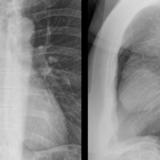

Case 8b Thymoma Lat

Date: 03/27/2009

Views: 14175